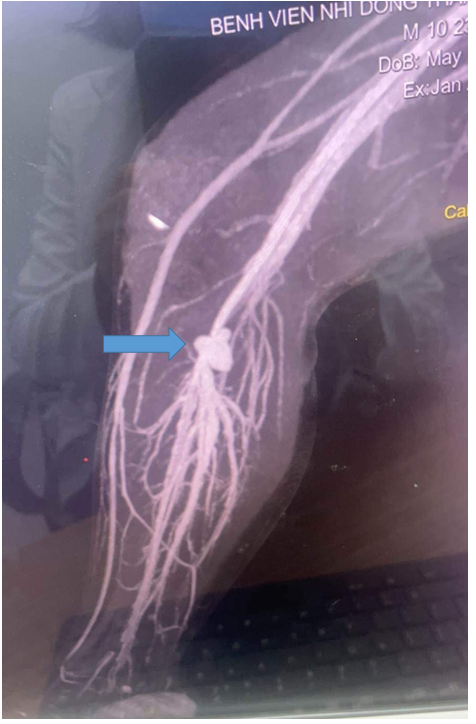

- Hẹp đoạn cuối động mạch khoeo, trước vị trí chia nhánh các mạch máu cẳng chân, kích thước tại vị trí hẹp d# 2,5mm, động mạch kheo sau vị trí hẹp đổ vào túi phình mạch máu lớn d# 22x15x18mm, từ túi phình mạch máu này chia nhánh ra toàn bộ các động mạch và tĩnh mạch cẳng chân bao gồm động tĩnh mạch chày trước chày sau và gian cốt. Ghi nhận nhiều nhánh động mạch bàng hệ vùng gối.

- Tắc đoạn cuối tĩnh mạch kheo tại vị trí túi phình, ghi nhận toàn bộ hệ tĩnh mạch cẳng chân , tĩnh mạch hiển lớn, hiển bé, tĩnh mạch đùi trái bắt thuốc tương phản rất sớm cùng lúc với động mạch do nhận máu từ túi phình động tĩnh mạch và qua các nhánh tĩnh mạch bàng hệ vùng gối và cẳng chân.